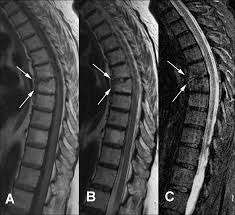

La infección por el virus de inmunodeficiencia humana (VIH) se ha asociado con una variedad de síntomas reumáticos, los cuales pueden coexistir con enfermedades reumáticas autoinmunitarias, tales como la artritis…